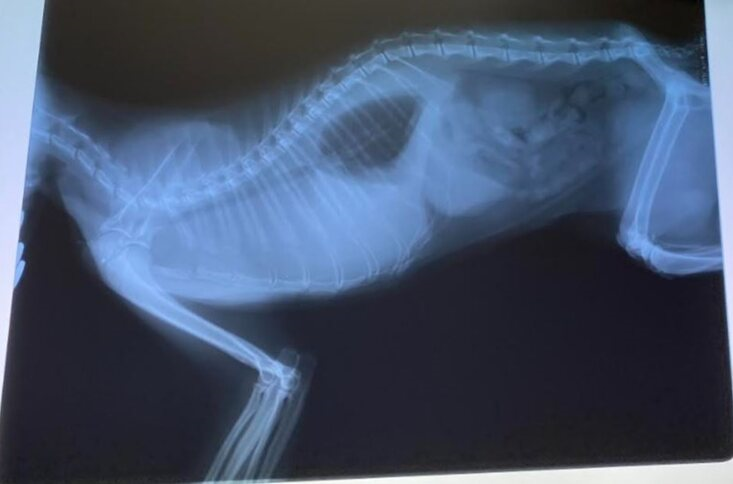

2020年5月に保護した子猫のクラダちゃんが、

2021年2月24日に、呼吸困難が見られました。

レントゲンを見たら、胸水が溜まっていました。

エコー検査も含めて、姫路動物病院の検査によると、

クラダちゃんは「FIPウェットタイプ中期」だと診断されました。